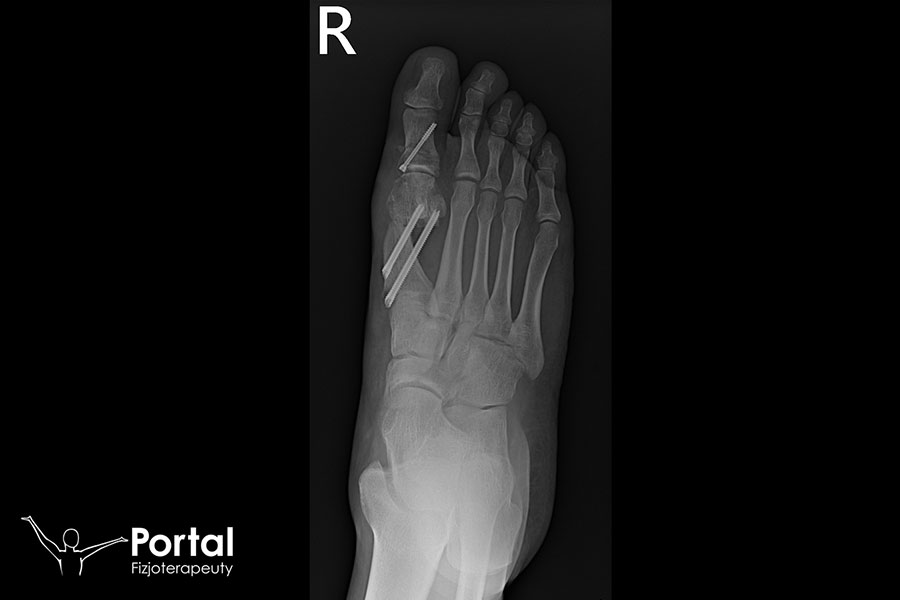

MICA

MICA (ang. Minimally Invasive Chevron Akin) to małoinwazyjna metoda przezskórna wykorzystywana w leczeniu palucha koślawego (potocznie: haluksa). Nie jest zabiegiem